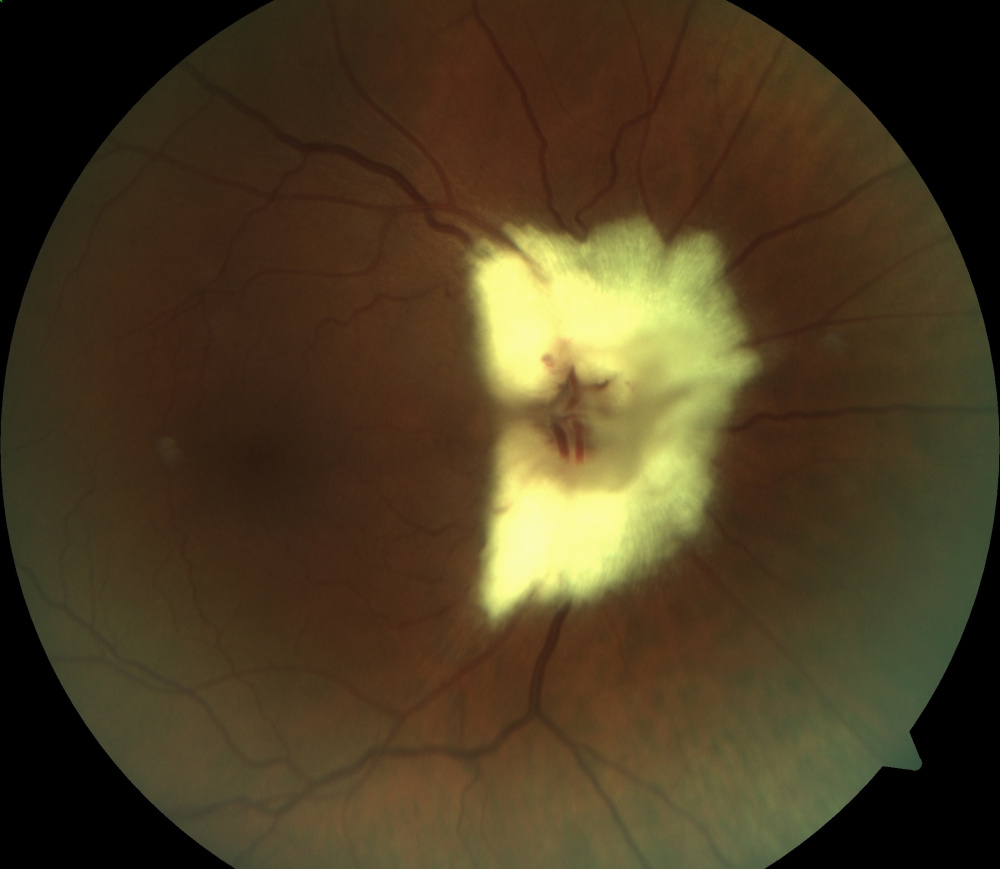

Título: Secondary Neovascularization Following Post-Traumatic Choroidal Rupture

Descrição: Secondary Neovascularization Following Post-Traumatic Choroidal Rupture